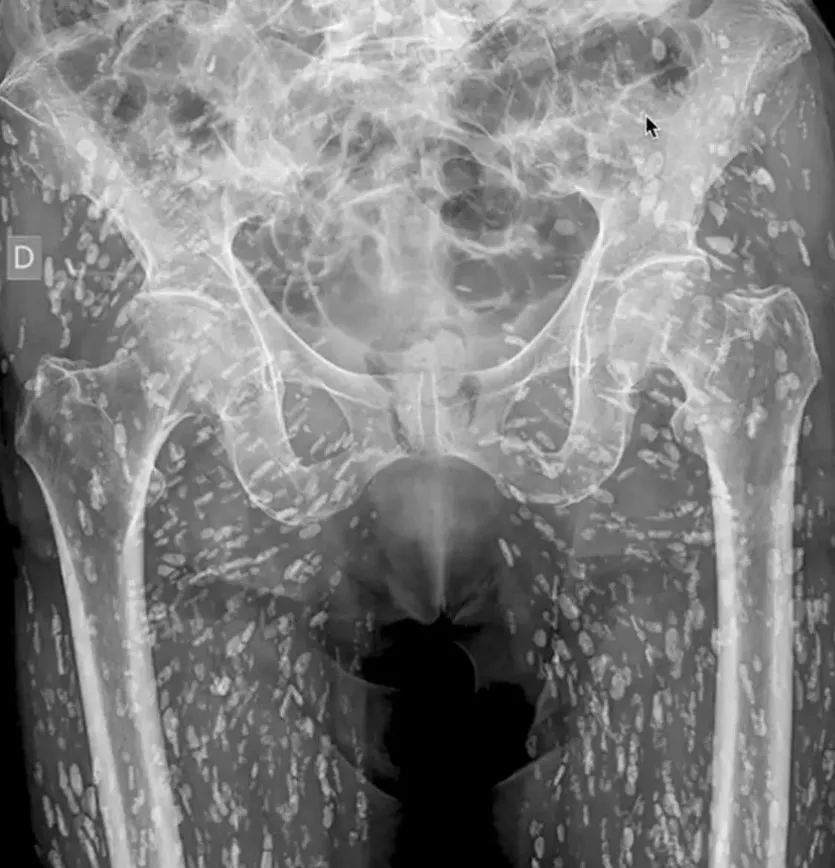

Et ‘chokerende’ røntgenbillede har afsløret en mand fyldt med hundredvis af bændelormeæg, som spredte sig i hans krop, fordi han lavede en alvorlig fejl i køkkenet.

Den amerikanske læge Sam Ghali delte billedet af den anonyme mand på det sociale medie X og beskrev det som “et af de mest utrolige røntgenbilleder, jeg nogensinde har set.”

“Dette er en tilstand kaldet cysticercose, hvor larvecyster fra Taenia solium – også kendt som svinebændelormen – findes i kroppen,” forklarede Ghali ifølge The Sun.

“Disse cyster kan sprede sig til mange steder i kroppen. I dette tilfælde har de i stor grad befundet sig i musklerne og det bløde væv i hofter og ben,” sagde han.

I dette tilfælde udgjorde cyster ikke en livstruende risiko. De blev heldigvis opdaget, da mandens hoftebrud blev afsløret på røntgenbilledet. Uden denne opdagelse kunne konsekvenserne have været alvorlige.